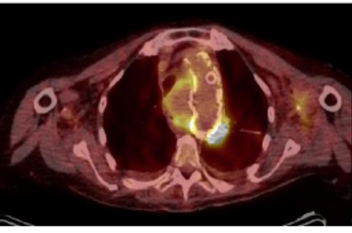

No complications were registered and there was a significant improvement in the patient’s previous symptomatology. Patient initiated broad spectrum antibiotics and underwent positron emission tomography (PET) revealing several metabolically active lymph nodes suggesting an underlying neoplasm, Figure 4. The patient was transferred to the area hospital on the eleventh day post-surgery to study underlying disease further.

Figure 4 Positron emission tomography scan showing metabolic activity in para-aortic lymph nodes and the aortic wall.